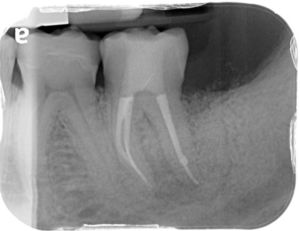

La pathologie pulpaire et les maladies parodontale partagent un organe cible commun : les tissus de soutien de la dent. Si leurs caractéristiques, leur diagnostic et leurs thérapeutiques propres sont habituellement aisés, la confluence sur une même racine d’une lésion parodontale et d’une lésion d’origine endodontique, aboutissant à une lésion endo-parodontale, complique largement autant le diagnostic que la thérapeutique.

La guérison de ces lésions combinées, relève de l’établissement d’un diagnostic précis et d’une thérapeutique adaptée.

Cette présentation a pour objectif de faire l’état des lieux des connaissances utiles à l’appréhension des lésions endo-parodontales (voies de communication, classifications) et d’illustrer les démarches diagnostiques et thérapeutiques à travers plusieurs cas cliniques.